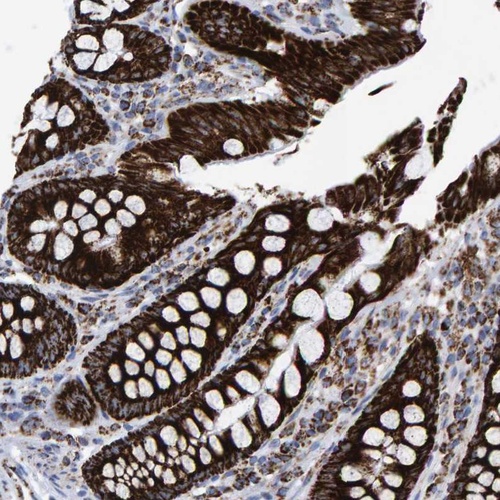

Immunohistochemical staining of human colon shows strong granular cytoplasmic positivity in glandular cells.